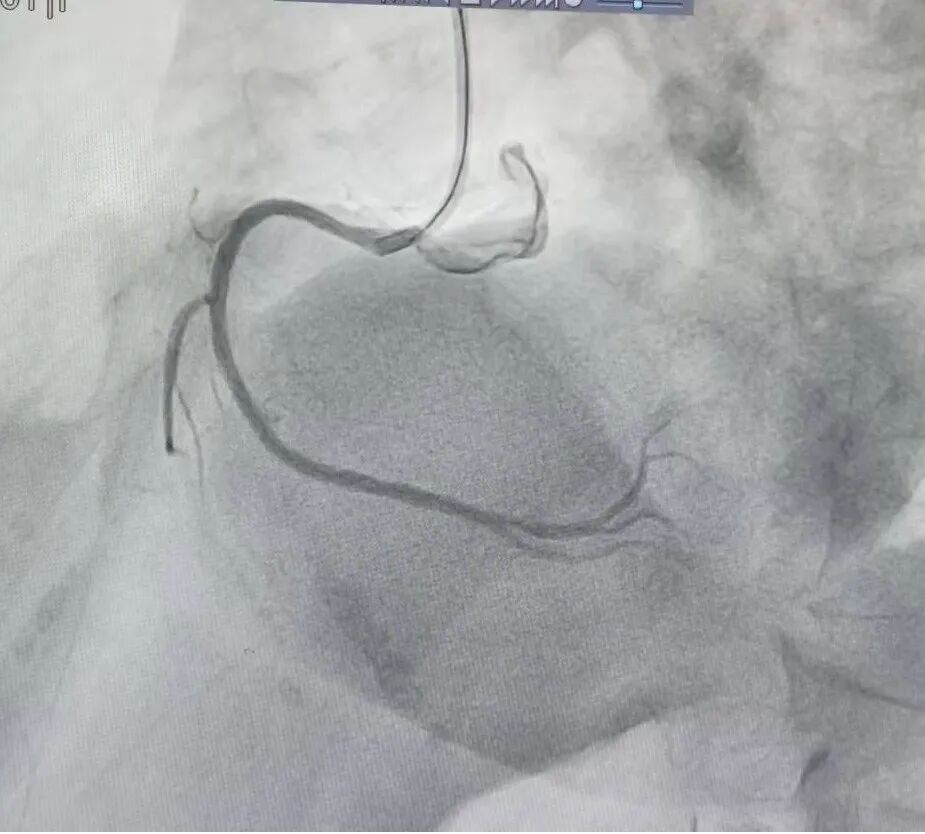

97岁高龄急性心梗获救!急诊PCI再创生命奇迹

手术台上,介入团队沉着冷静、精准操作,顺利将导丝通过闭塞病变,成功开通梗死相关血管,恢复心肌灌注,全程患者生命体征平稳,手术圆满成功。术后,医护团队精心制定监护与康复方案,24小时密切观察病情、精准调整用药、悉心照料饮食起居,帮助老人平稳度过危险期,从命悬一线逐步好转直至康复出院。

此次超高龄急性心梗患者的成功救治,它打破了高龄患者不宜手术的传统观念,解释了年龄并非介入手术的绝对禁忌,只要科学评估、精准施治,高龄患者同样可以重获健康。这既是医疗技术的突破,更是医院始终坚持以患者为中心、不放弃任何一位患者的生动诠释。在人口老龄化不断加深的今天,此次成功案例为高龄急危重症心血管疾病救治积累了宝贵经验,也让更多高龄患者及家属看到希望。未来,医院将继续坚守医者使命,精进医疗技术、优化急救流程,着力打造一所“无差别